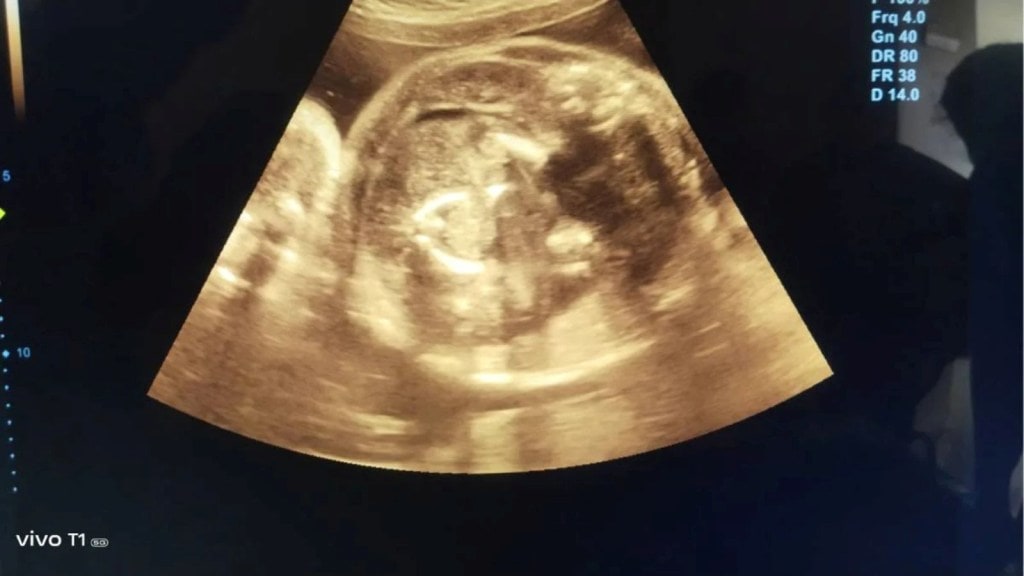

નાગપુરના બુલઢાણા શહેરના પ્રખ્યાત પ્રસૂતિ નિષ્ણાત રસાદ રાજકુમાર અગ્રવાલ, સ્થાનિક સરકારી મહિલા હોસ્પિટલમાં સેવાઓ પૂરી પાડે છે. તેમની પાસે સારવાર માટે આવેલી બત્રીસ વર્ષની અને નવ મહિનાની સગર્ભા સ્ત્રીની તેણે 'સોનોગ્રાફી' કરી ત્યારે તેમને 'કંઈક અલગ' જણાયું! તપાસમાં તેમને માત્ર મહિલાના ગર્ભમાં બાળક જ નહીં પરંતુ બાળકના પેટમાં 'બાળક' પણ જોવા મળ્યું. જેથી ડો.પ્રસાદ અગ્રવાલે બે-ત્રણ વખત તપાસ કરતાં બાળકના પેટમાં બાળક હોવાનું સ્પષ્ટ થયું હતું.

ડૉ. અગ્રવાલે જણાવ્યું હતું કે, આ સંદર્ભે જિલ્લા સર્જન, સરકારી મેડિકલ કોલેજના પ્રિન્સિપાલ ઝીને, મહિલા હોસ્પિટલના મેડિકલ સુપરિન્ટેન્ડેન્ટ ડૉ. પાટીલે માહિતી આપી હતી. સિનિયર્સના માર્ગદર્શન હેઠળ ફરી સોનોગ્રાફી કરવામાં આવી. બાળકના પેટમાં બાળક સ્પષ્ટ દેખાતું હતું. આ મહિલાને પ્રસૂતિની સુવિધા આપવા અને જોખમ વિના બાળકને જન્મ આપવા માટે છત્રપતિ સંભાજી નગર ખાતે ખસેડવામાં આવી છે.

અગ્રવાલે જણાવ્યું તે, બાળકના ગર્ભમાં રહેલું બાળક સંપૂર્ણ રીતે વિકસતું નથી. જોડિયા જન્મે ત્યારે આવું થઈ શકે છે. મૃત શિશુને બાળકના પેટમાંથી કાઢી શકાય છે. ડિલિવરી જટિલ હોવાથી અમે તેને સંભાજીનગર મોકલવાનું નક્કી કર્યું છે.